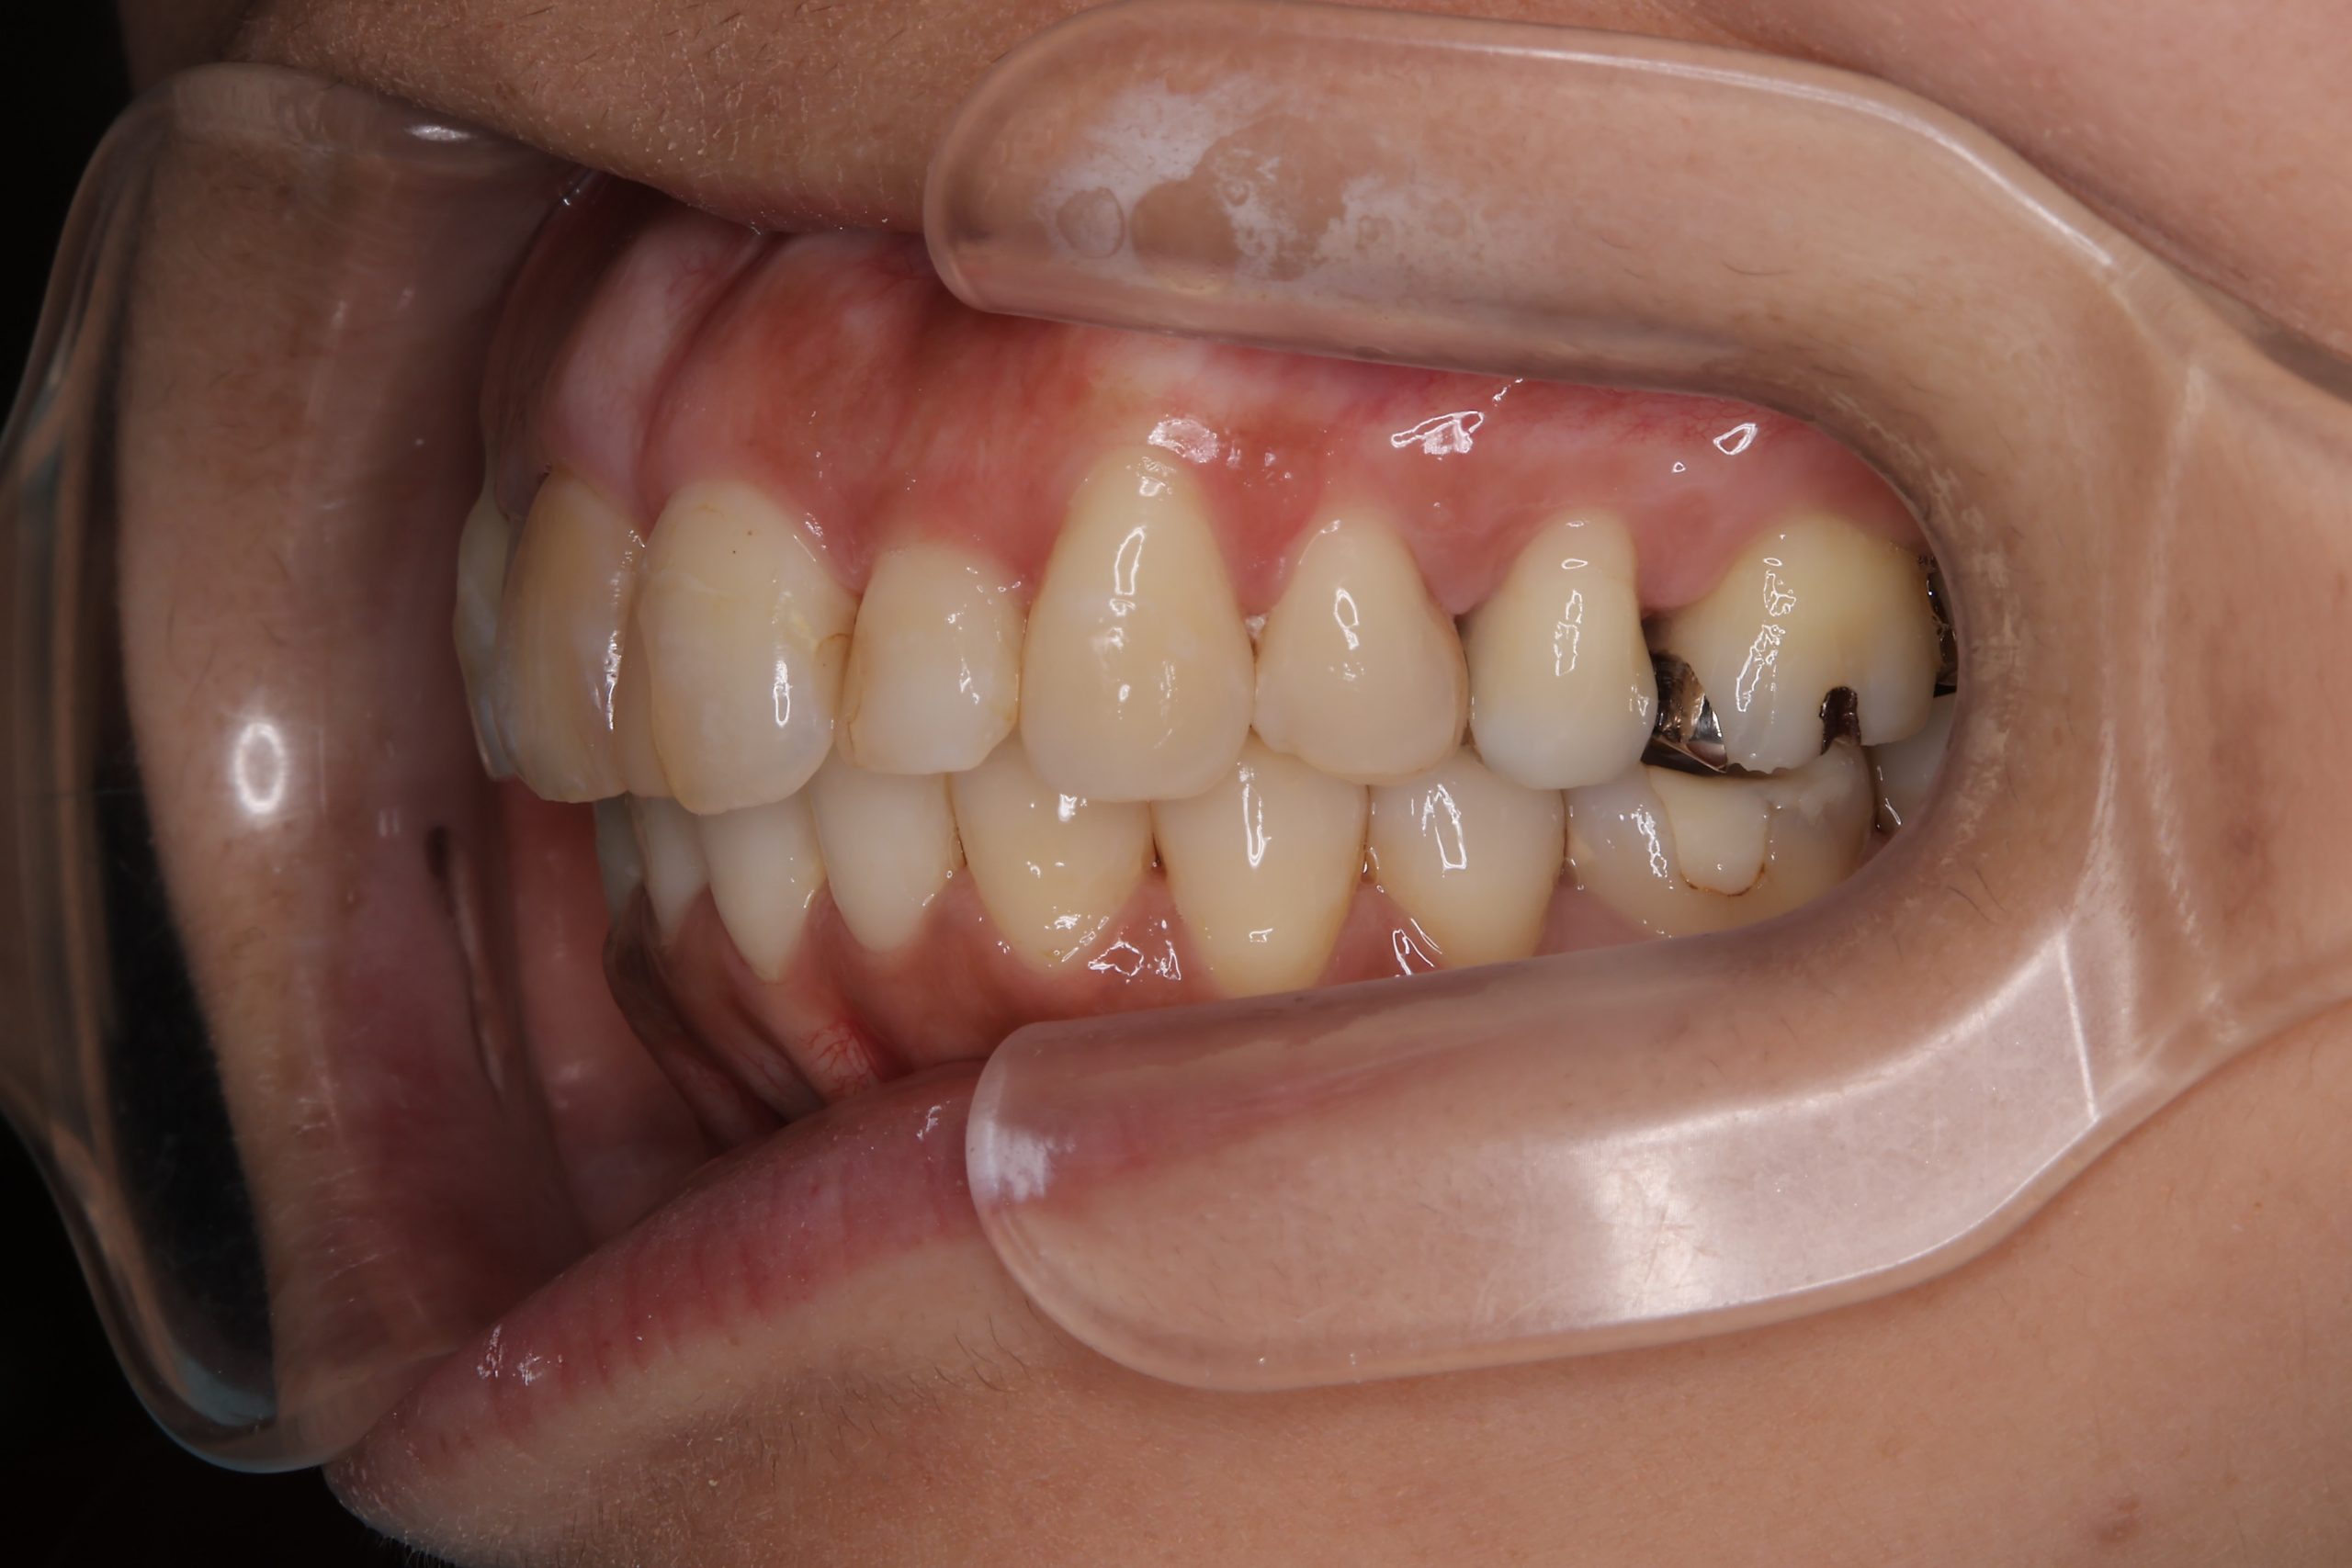

インビザライン矯正治療|症例_649